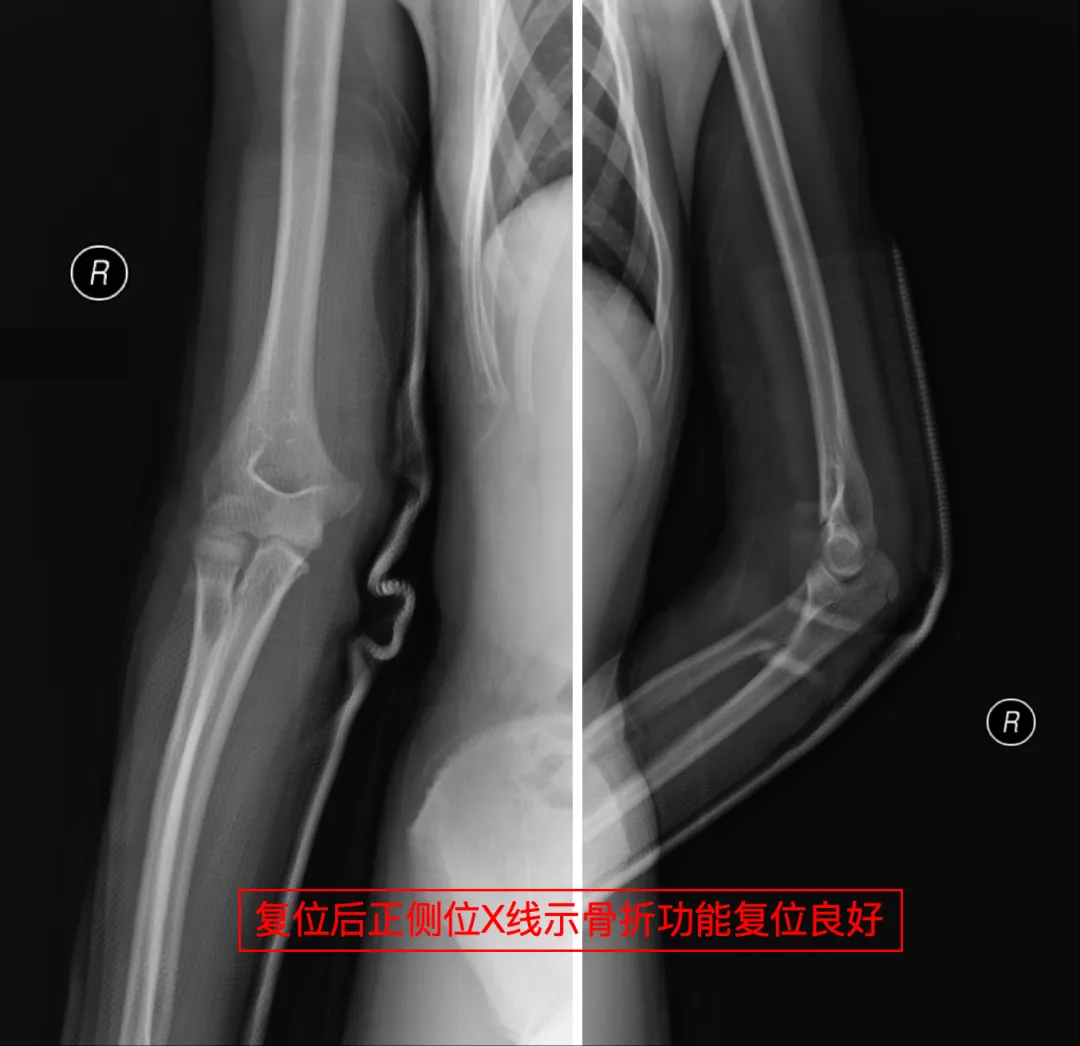

急匆匆询问了一下本地人,她们来到威海卫人民医院手足外科就诊。拍片、诊断、复位、固定,整个迅速又专业的诊疗过程让李妈妈深感意外,主诊医生的精湛操作让孩子免于手术创伤,更令李女士动容的是无处不在的人文关怀医护人员耐心解答、细致指导,导医护士主动帮忙……最让李妈妈感动的是,接诊医生得知她们是外地游客,特意把复查时间安排得相对灵活。